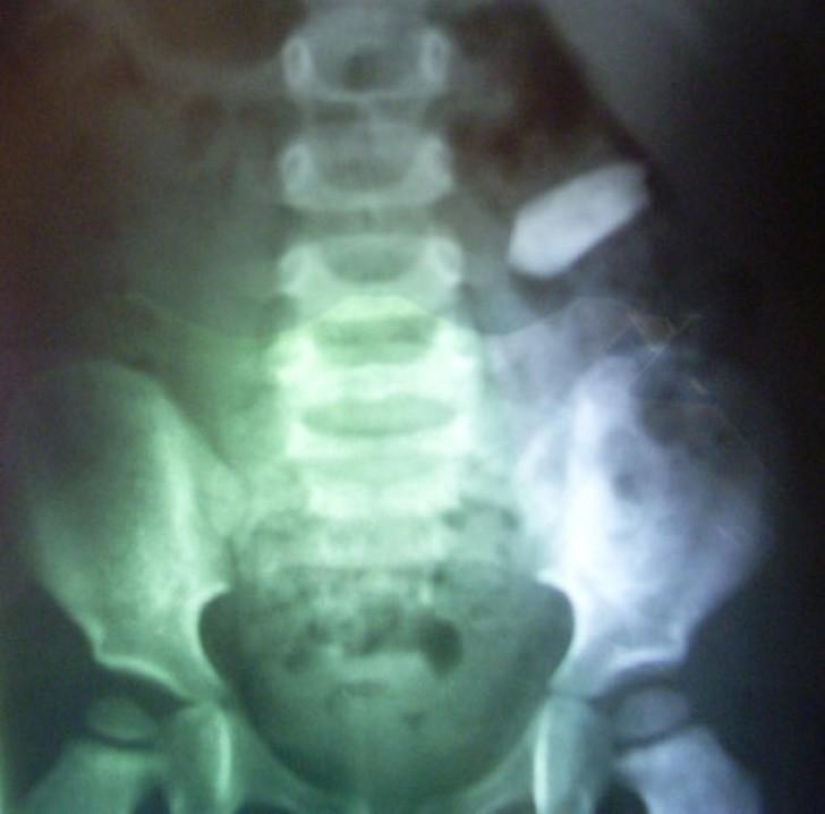

Huge ball of wool.